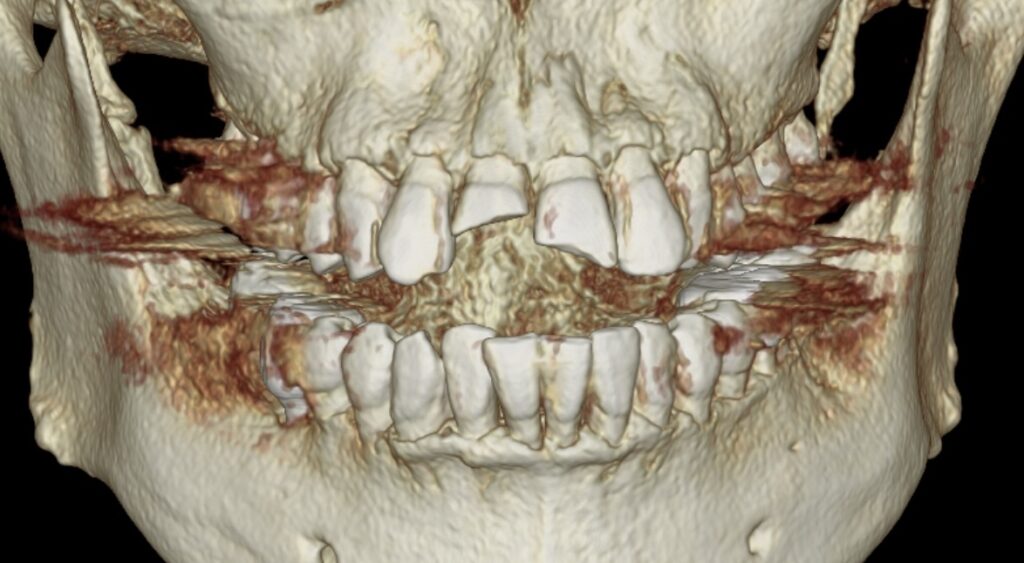

치아 외상으로 인해

크게 이가 부러졌다면,

방사선 촬영을 통해

이를 잡아주는 치조골에는

문제가 없는지 확인을 해야 되는데요.

2025.02.12

촬영본을 확인해 보았을 때

협측 치조골의 골절이 있는 것으로 보아

이가 흔들릴 것으로 판단되며,

치아 고정술이 필요해 보입니다.